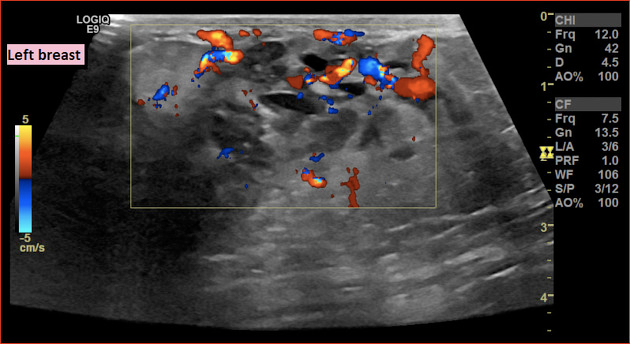

US

• Epaississement cutané

• Oedème

• ADP

sein mammaire